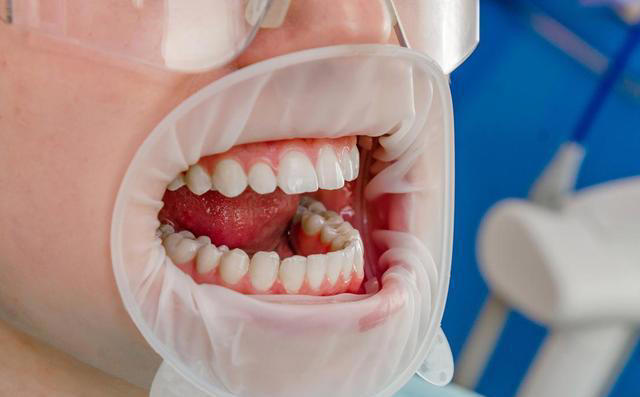

很多人习惯每天早晚各刷一次牙,认为这样就能保证口腔健康。然而,有些人的牙齿却依然出现了问题,可能在刷牙时没有注意到一些细节,导致了口腔健康的下降。 比如56岁的李阿姨,她一直早晚按时刷牙,却常常感到口腔不清新,牙齿也变得松动了。 医生告诉她,可能是因为她一直保持着一些不太合适的刷牙习惯,特别是在60岁以后,一些习惯如果不改掉,可能会给口腔带来隐患。

事实上,随着年龄的增长,我们的口腔也会发生一些变化。比如牙齿容易变脆,牙龈容易退缩,这些都需要我们在刷牙时更加小心,采取一些不同的护理方式。 首先,很多人认为早晚各刷一次牙就足够了,但实际上,早晚刷牙并不是最理想的方式。 特别是对于60岁以上的人群来说,早晚刷牙可能并不能彻底清洁口腔。 早上起床后,口腔内有大量的细菌和食物残渣,光是早晨刷牙可能不能彻底清除这些东西,而晚上刷牙时,很多人又容易忽视牙齿缝隙中的食物残渣。

随着时间的推移,这些细菌会积累,进而影响到牙齿和牙龈的健康。 医生建议,老年人可以考虑一天刷三次牙,特别是餐后及时刷牙,这样可以更有效地清除口腔中的细菌和残渣,减少口腔问题的发生。 另外,很多人习惯用硬毛牙刷刷牙,认为这样可以更彻底地清洁牙齿。 但是,过硬的牙刷毛容易对牙龈造成刺激,甚至可能导致牙龈出血和退缩,尤其对于老年人来说,牙龈退缩的风险更高。老年人的牙龈本身就较为脆弱,如果再使用硬毛牙刷,可能会加重退缩的情况。 医生建议,老年人最好选择软毛牙刷,这样既能有效清洁牙齿,又不容易伤害牙龈。

再有,刷牙时很多人都会用力过猛,认为这样可以刷得更干净。 其实,用力过猛不仅不会更有效地清洁牙齿,反而会加剧牙龈的磨损,甚至可能导致牙齿松动。刷牙时我们应该保持适当的力度,牙刷与牙齿之间的角度大约为45度,用轻柔的画圈动作刷牙,这样可以有效清洁牙齿,又不会对牙龈造成伤害。 此外,很多人刷牙时忽略了舌头的清洁。 舌头上有大量的细菌,如果不及时清洁,很容易导致口气不清新,甚至可能引发口腔疾病。对于老年人来说,舌头上的细菌积聚可能会影响到整体口腔健康。 因此,医生建议,每次刷牙时,也要轻轻刷刷舌头,保持舌面的清洁。